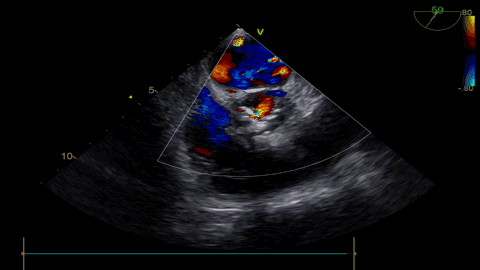

球扩后超声

发生瓣叶切割,无窦侧瓣叶切割,Type0结构形变为类三叶瓣结构。

超声显示人工瓣膜工作良好,微量瓣周漏,术后一周顺利出院,术后随访无并发症,恢复良好。